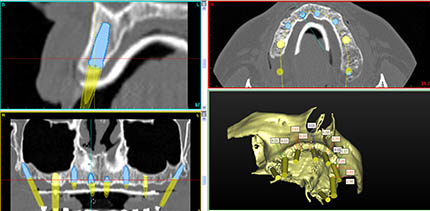

IMPLANTES GUIADOS POR ORDENADOR SIN INCISIONES NI SUTURAS:

Realizando un TAC al paciente procesado mediante un avanzado software 3D,

Realizamos una reconstrucción digital de los maxilares, donde podemos planificar cada caso como si fuese una cirugía previa y fabricar una férula quirúrgica que nos sirve de guía para para insertar los implantes en idéntica posición que habiamos hecho en el ordenador sin incisiones ni puntos.